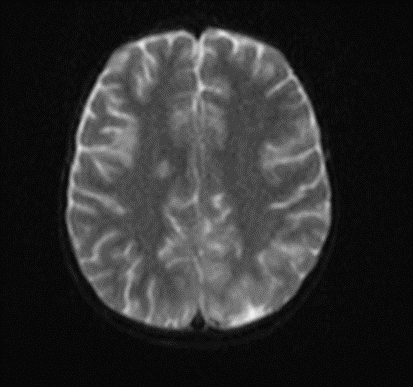

Subsequently, an MRI of the brain was performed, which demonstrated: Bilateral diffuse high signal changes in the cerebellum on T2 and FLAIR sequences, as well as areas of restricted diffusion, indicating focal zones of cytotoxic edema.

Picture 2.